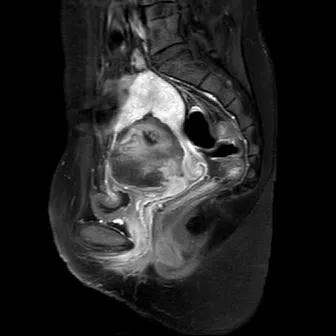

33岁的刘女士是沧州人,在一年多以前因患子宫腺肌瘤在当地接受了经腹子宫腺肌瘤切除术,后来又进行试管婴儿受孕,但是2个月前,这个让她满心期待了四个多月的小生命又在妈妈的子宫内暂停了旅程,刘女士只能通过药物引产将死胎娩出。但是,引产之后胎盘未能完全排出,刘女士接受清宫手术来清除残留胎盘。术后复查时,妇科彩超提示子宫杂乱回声团,考虑为胎盘植入,经核磁检查发现,胎盘植入处于之前子宫腺肌瘤挖除处,病灶大小约8×6×6厘米。

治疗前的超声造影显示,病灶中间血流灌注非常明显,海扶手术后再看,病灶中心已经没有明显血流灌注了。病灶失去了血流供应,相当于没有了供给,这一部分变性坏死的组织就会被吸收或脱落被排出。